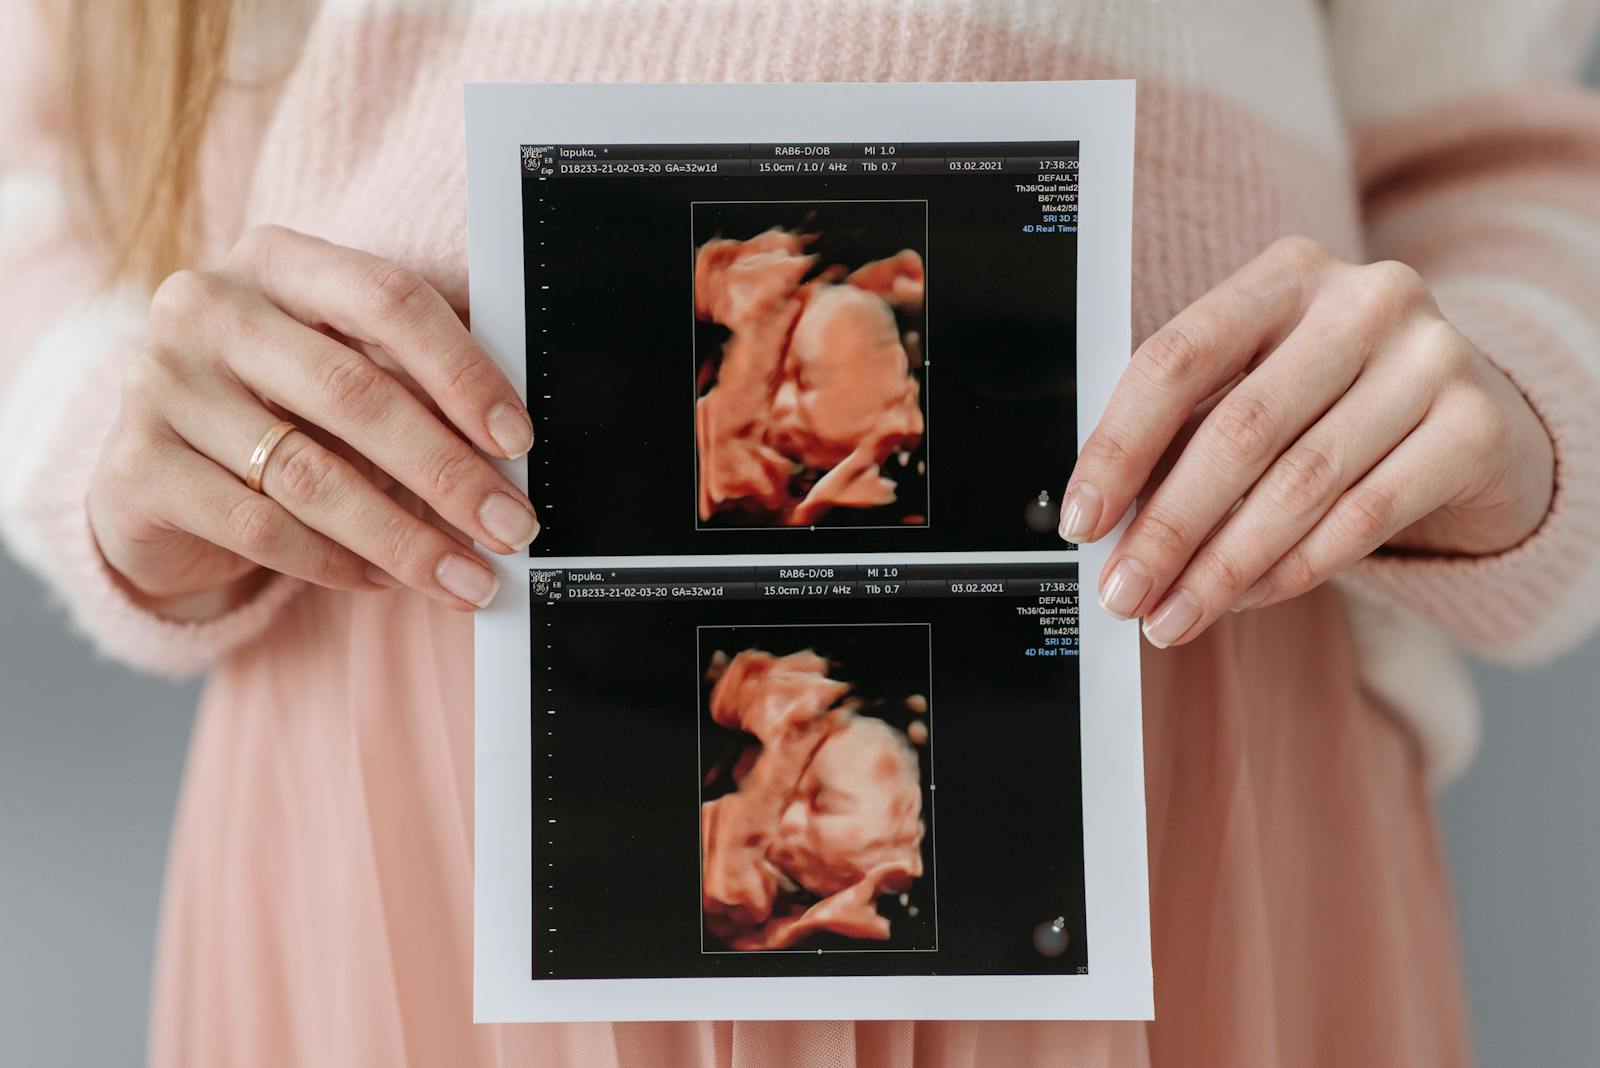

Twin & Multiple Pregnancies

Dedicated care for the unique demands of carrying more than one baby.